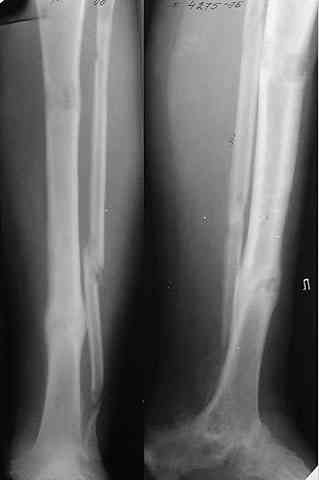

Глубокоуважаемые коллеги! Просим совета в лечении пациента с последствиями тяжелой сочетанной травмы. Пациент С., 41 года, по профессии бизнесмен, в сентябре 2005 г. пострадал в дорожно-транспортном происшествии (упал с мотоцикла). Диагноз: ЗЧМТ, ушиб головного мозга тяжелой степени. Открытый переломо-вывих левой таранной кости. Закрытые переломы лонной и седалищной костей слева. Был доставлен в НИИСП им. Н.В. Склифосовского. При ПХО раны выявлен открытый перелом левой таранной кости (III тип по Hawkins) с утратой вывихнутого тела таранной кости. Выполнена ПХО, фиксация голени и стопы стержневым аппаратом. Рана зажила без осложнений. Аппарат демонтирован через 1,5 месяца. В настоящее время больной предъявляет жалобы на боль в голеностопном суставе при нагрузке. Передвигается с опорой на костыли с дозированной нагрузкой на левую стопу.Голень и стопа фиксированы циркулярной пластиковой повязкой. Сохраняются остаточные явления ЧМТ (в виде сниженной критики к своему состоянию и определенной недисциплинированности в выполнении врачебных рекомендаций) Рентгенограммы – рис. 1, 2 (просим извинения за низкое качество рентгенограмм), схема – рис. 3. В качестве варианта хирургического лечения мы считаем возможным выполнить следующее вмешательство: артродез большеберцовой и пяточной костей в сочетании с артродезом переднего края большеберцовой кости и головки таранной кости с фиксацией спонгиозными винтами. Считаем выполнение артродеза переднего края большеберцовой кости и элементов I луча стопы необходимым для максимального восстановления опороспособности конечности. Однако выполнение операции в указанном объеме привело бы к относительному укорочению внутреннего свода стопы. Мы видим два пути решения данной проблемы: Вариант 1. Применение костного трансплантата (свободного или на сосудистой ножке) для замещения дефекта головки таранной кости и сохранения геометрии внутреннего свода стопы (рис 4). Преимущество: относительная простота операции. Недостаток: высокий риск замедленной консолидации или лизиса трансплантата. Вариант 2. Резекция участка пяточной кости с последующим остеосинтезом винтами для укорочения наружного свода стопы (рис 5, 6). Преимущества: сохранение собственного кровоснабжения всех синтезируемых участков костей. Недостатки: дополнительная травматизация, усугубление деформации стопы в виде нарушения наружного свода. Будем признательны за ваши предложения, включая возможные альтернативные варианты лечения.Заранее благодарны за добрые советы и поддержку. А. Федосов, О. Диденко, П. Иванов. Отделение множественной и сочетанной травмы НИИСП им. Н.В. Склифосовского, г. Москва.